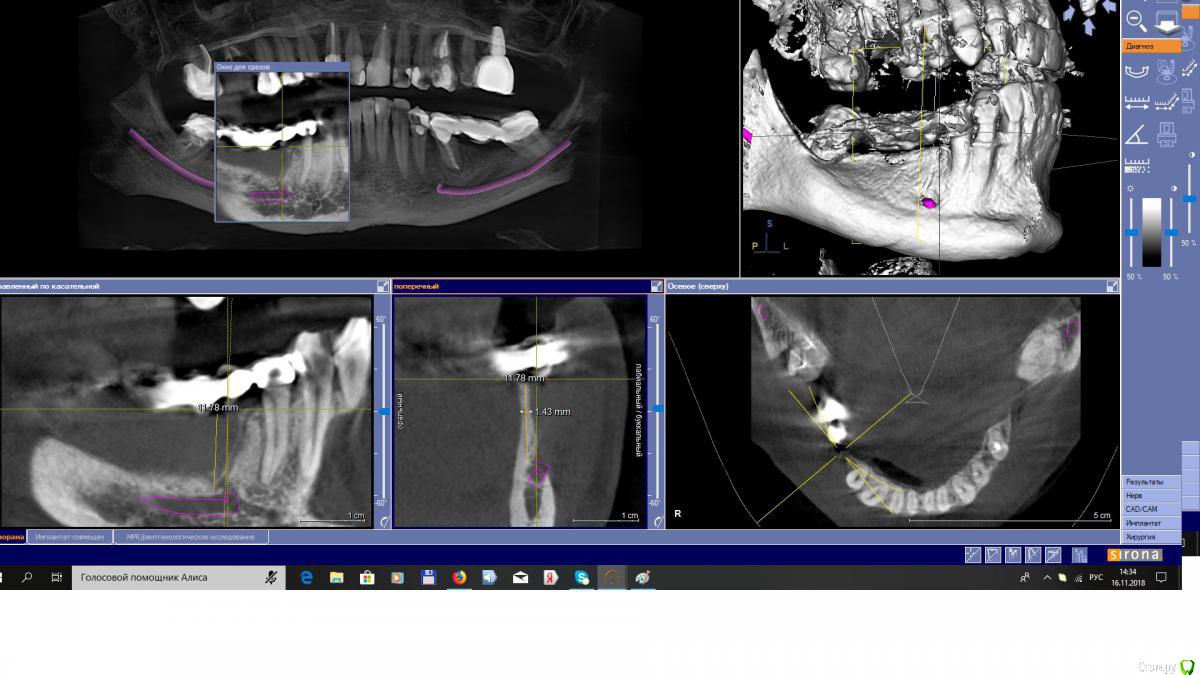

EEcho Опубликовано 16 ноября, 2018 Поделиться Опубликовано 16 ноября, 2018 Коллеги, добрый день!Ваши варианты при такой атрофии. Ссылка на комментарий

EEcho Опубликовано 22 ноября, 2018 Автор Поделиться Опубликовано 22 ноября, 2018 Это понятно, что можно любую методику кроме расщепления и моноблоков, но как в этом случае обойти ментальное отверстие с выходом сосудисто-нервного пучка почти вертикально? Резать мембрану обходя отверстие и бить кнопки вокруг, то есть сосиську по Урбану, с эволюшкой.? или делать каркас из мини пластин.? полужестким каркасом отверстие будет не обойти.( возможно графт будет через него высыпаться или врастет через него соединительная ткань)? Ссылка на комментарий

АнтонТЛТ Опубликовано 22 ноября, 2018 Поделиться Опубликовано 22 ноября, 2018 Если ментальное отверстие напрягает, нарастить до него и поставьте имплантат покороче 1 Ссылка на комментарий